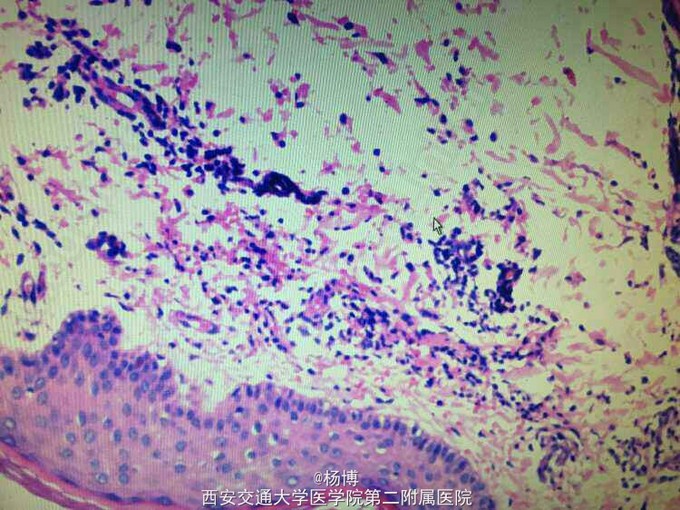

病理诊断结果为:“?部”小块皮肤组织,表皮角化过度,基底层色素增加,真皮浅层小血管周围有多量淋巴细胞,中性粒细胞浸润,片内结构结合临床,符合变应性血管炎改变。